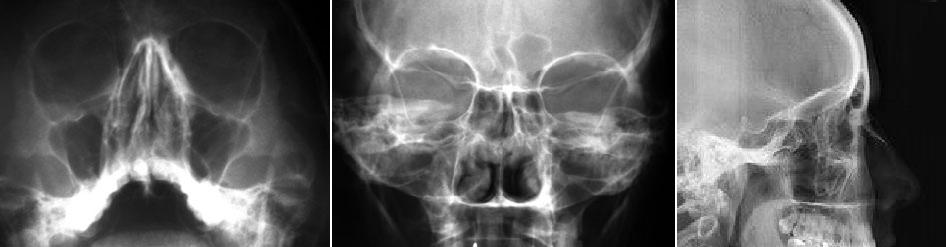

Radiografias de senos

Es cierto que un seno opacificado y/o un nivel hidroaereo pueden aparecer en la sinusitis. Pero con frecuencia un paciente con estos hallazgos es asintomatico; con la misma frecuencia, unas radiografias de senos interpretadas como normales corresponden a un paciente con hallazgos clinicos tipicos de sinusitis. En ambos casos los pacientes son tratados basandose en su presentacion clinica, no radiografica, lo que, por otra parte, es adecuado. En fin, se prescinde de la informacion de las radiografias de senos. Si usted tambien trabaja asi –como recomiendan la mayor parte de los autores~ no pida radiografias de senos: trate al paciente. Reserve las radiografias de senos para el paciente que no responde al tratarniemo o que tiene una presentacion inusual. Ademas, si lo que le preocupa es solo la sinusitis, suele ser suficieme una simple proyeccion de Waters con rayo horizontal para examinar los senos maxilares y frontales, en lugar de una serie completa de senos, lo que

permite ahorrar dinero y disminuir la exposicion al paciente.

Huesos propios de la nariz

Muchas veces se pide una radiografia de los huesos propios para ver si el paciente tiene una fractura nasal tras un traumatismo facial. Y que

mas da si los huesos nasales estan fracturados? No se van a escayolar ni se va a reducir. En otros terminos, no se va a realizar tratamiento, independiemtemente de lo que muestre la radiografia. Por lo tanto, no pida estas placas en el primer momento. En ocasiones, los huesos nasales pueden estar suficientemente desplazados como para justificar la intervencion, pero incluso entonces la radiografia en el momemo postraumatico agudo no añade al paciente nada mas que gasto y exceso de radiacion. Si pueden estar indicadas placas del macizo facial para buscar otras fracturas,

pero no las radiografias de huesos propios de la nariz.